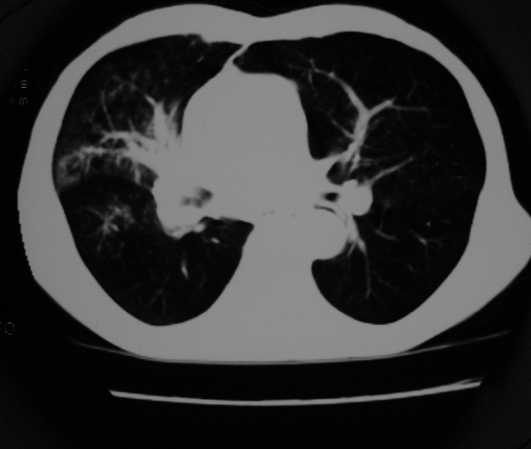

以下是引用同在2007-1-27 14:13:00的发言:[br]支持右侧中央型肺癌伴阻塞性病变.

以下是引用zjzjr在2007-1-27 16:56:00的发言:[br]支持右肺中心型肺癌伴阻塞性肺炎.